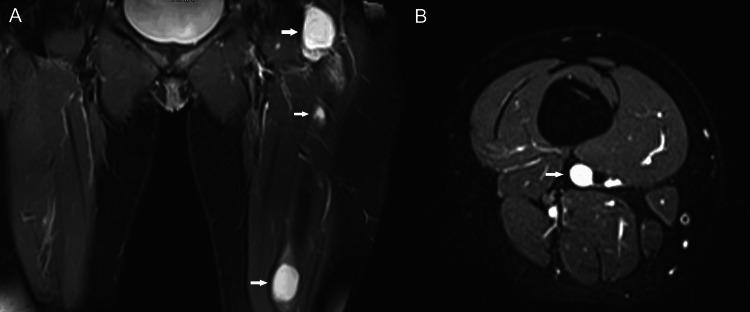

Mazabraud syndrome is a rare condition characterized by the coexistence of fibrous dysplasia (FD) and intramuscular myxomas. A 46-year-old woman, initially diagnosed with polyostotic FD at the age of 23, developed a palpable mass on her left arm 15 years later, which proved to be an intramuscular myxoma. A diagnosis of Mazabraud syndrome was made. Over the following two decades, she developed additional intramuscular myxomas. The patient denied surgical excision of the soft tissue lesions and was managed conservatively for symptomatic FD. Radiologic imaging, including MRI and ultrasound, played a crucial role in the diagnosis and the assessment of disease progression. Although both FD and myxomas are benign musculoskeletal abnormalities, close follow-up of the patients is essential to monitor changes in the number, distribution, and extent of lesions that may occasionally undergo malignant transformation. This case underscores the importance of early detection and long-term follow-up of patients with FD who may present with, or eventually develop, intramuscular myxomas, comprising Mazabraud syndrome.

马扎布劳德综合征是一种罕见疾病,其特征为骨纤维发育不良(FD)和肌内黏液瘤并存。一名46岁女性,23岁时最初被诊断为多骨型FD,15年后左手臂出现一个可触及的肿块,经证实为肌内黏液瘤。遂作出马扎布劳德综合征的诊断。在接下来的二十年里,她又出现了其他肌内黏液瘤。该患者拒绝手术切除软组织病变,对有症状的FD采取保守治疗。包括MRI和超声在内的放射学成像在疾病诊断和病情进展评估中发挥了关键作用。尽管FD和黏液瘤均为良性肌肉骨骼异常,但对患者进行密切随访对于监测可能偶尔发生恶变的病变的数量、分布和范围变化至关重要。该病例强调了对可能出现或最终发展为肌内黏液瘤(构成马扎布劳德综合征)的FD患者进行早期检测和长期随访的重要性。